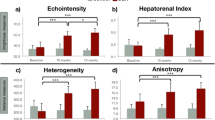

US-Red% analyzed in relation to liver fibrosis stage

When US-Red% was analyzed in relation to liver fibrosis stage, median US-Red% was 5.2 (2.9–6.1) % for F1, 7.1 (4.1–9.3) % for F2, 8.7 (5.1–12.5) % for F3, and 8.9 (3.6–15.7) % for F4. Thus, US-Red on B-mode image tended to be more abundant with progression of liver fibrosis stage (Fig. 4). US-Red% increased significantly as the liver fibrosis stage progressed (P = 0.70, P < 0.001; Fig. 5). However, the US-Red% results varied widely in cases of F4. When cases of F4 were excluded from the analysis and only cases of F1 through F3 were analyzed, a stronger positive correlation was noted between US-Red% and liver fibrosis stage (P = 0.76, P < 0.0001).

US-Red% analyzed in relation to percent liver fibrosis

When percent liver fibrosis was analyzed in relation to liver fibrosis stage, Percent liver fibrosis was 2.1 (0.8–6.7) % for F1, 3.7 (2–7.7) % for F2, 8.8 (5.3–12.2) % for F3, and 13.8 (2.8–18) % for F4. Thus, percent liver fibrosis increased significantly as the liver fibrosis stage progressed (P = 0.85, P < 0.001; Fig. 6a). US-Red% tended to increase with increasing percent liver fibrosis, but the correlation was not statistically significant (P = 0.18; Fig. 6b).

US-Red% analyzed in relation to nodule size and fibrous septum thickness in cases of F4

Because the results of US-Red% varied widely in cases of F4 (n = 22), we histologically divided these cases according to nodule size and fibrous septum thickness.

Nodule size was small in six cases, mixed in nine cases, and large in seven cases. When US-Red% was analyzed in relation to nodule size, US-Red% was 6.6 (3.6–8.3) % in the small group, 6.9 (4.2–14.5) % in the mixed group, and 9.9 (9.4–15.7) % in the large group. Thus, US-Red% differed significantly depending on nodule size (P = 0.016). That is, there were significant differences in US-Red% between the small group and the large group (P < 0.05; Fig. 7a), although there were no significant differences in US-Red% between the small group and the mixed group or between the mixed group and the large group.

a Comparison of US-Red% for three groups by size of nodule in cirrhosis. There was a significant difference among the three groups, and between the small group and the large group (*P < 0.05, Turkey test). b Comparison of US-Red% for three groups by width of fiber septum in cirrhosis. There was no significant difference among the three groups

Fibrous septum thickness was thin in ten cases, mixed in seven cases, and thick in five cases. When US-Red% was analyzed in relation to fibrous septum thickness, US-Red% was 6.8 (3.6–10.6) % in the thin group, 9.9 (6.1–15.7) % in the mixed group, and 9.8 (6.9–14.5) % in the thick group. US-Red% tended to increase as the septum became thicker, but there were no significant differences in US-Red% between any two of the three categories of septum thickness (Fig. 7b).